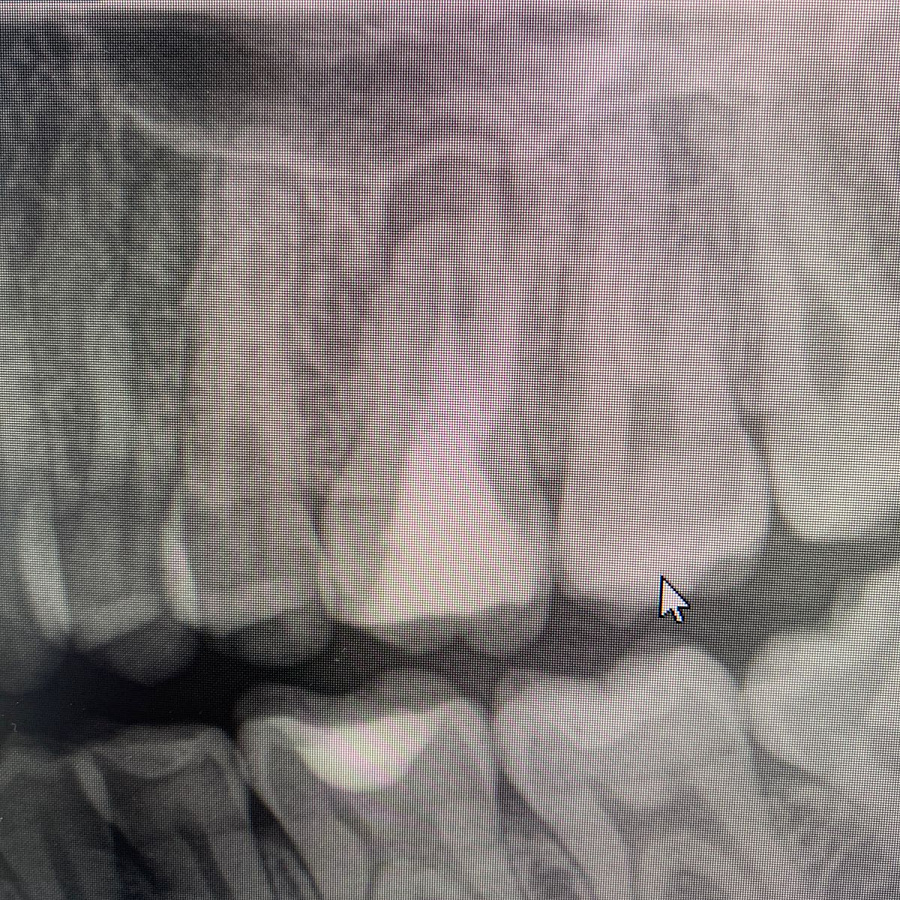

В ходе эндодонтической диагностики доктор обнаружил трещину в корне зуба.

Сохранить или вылечить зуб невозможно, поэтому было рекомендовано удаление зуба с последующей имплантацией.

После удаления таких зубов и извлечения кисты, в кости остаётся большой дефект. Поэтому сделать одномоментную имплантацию зуба, т.е. удаление и имплантацию за один приём невозможно. В таких случаях необходимы дополнительные хирургические манипуляции по подсадке искусственной кости, чтобы сохранить объём костной ткани для последующего протезирования.

Через 6 месяцев после подсадки кости - контрольный снимок и установка зубного имплантата.